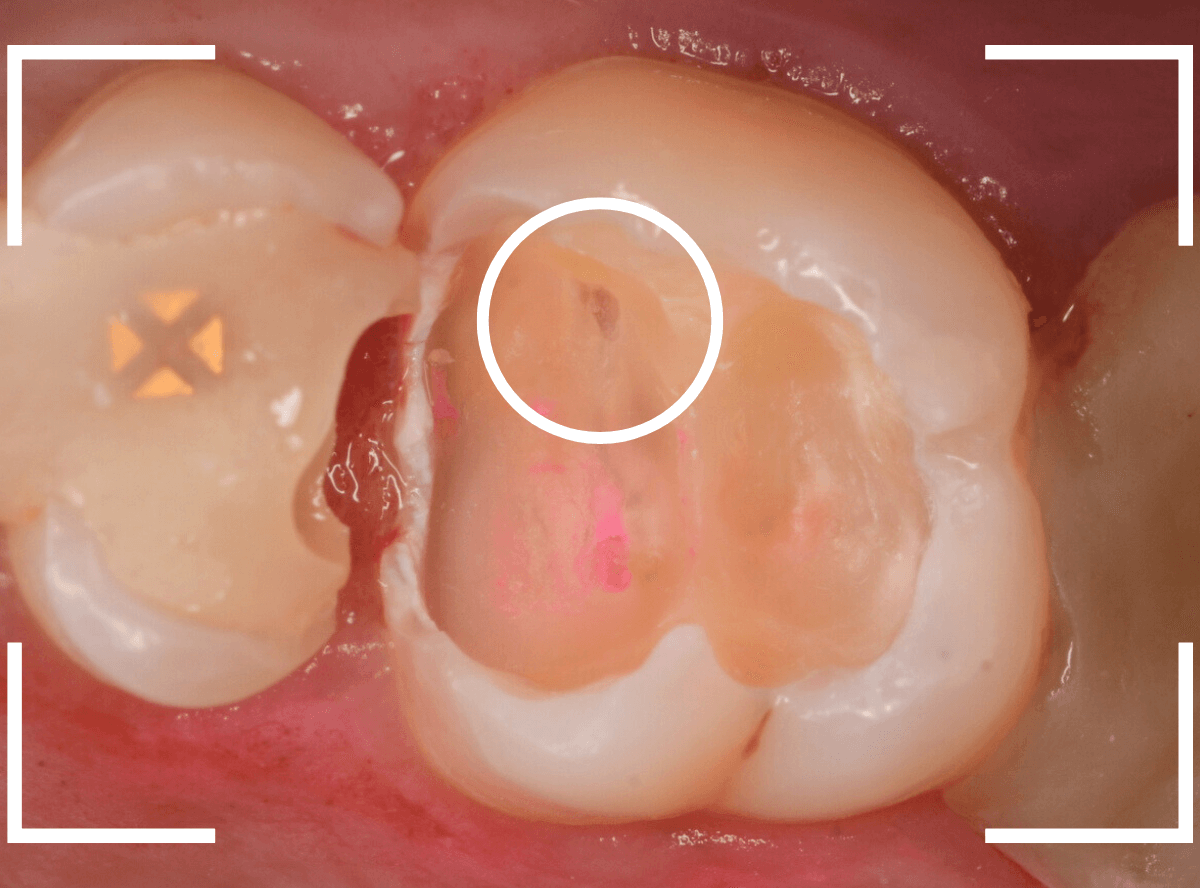

奥歯で咬んだ時に、痛みを感じるという訴えで来院された患者さんです。

パッと見は特に問題なさそうな状態ですが、大きなレジン治療がしてあり、レジンの奥もボヤっと黒っぽく見えてアヤシイ感じです。

麻酔をして、治療を開始します。

レジンを外すと、中から出血してきました。

これは、歯のスキマに歯肉が入り込んでしまったために起こってしまったものです。

おそらく、随分前から虫歯が進行していたと思われます。

慎重に全ての虫歯を除去したところです。

〇部が神経の入り口が見えているところです。

神経を保護する処置をして、しばらく経過観察しますが、痛みが出て神経を除去する必要が出る可能性も高いです。